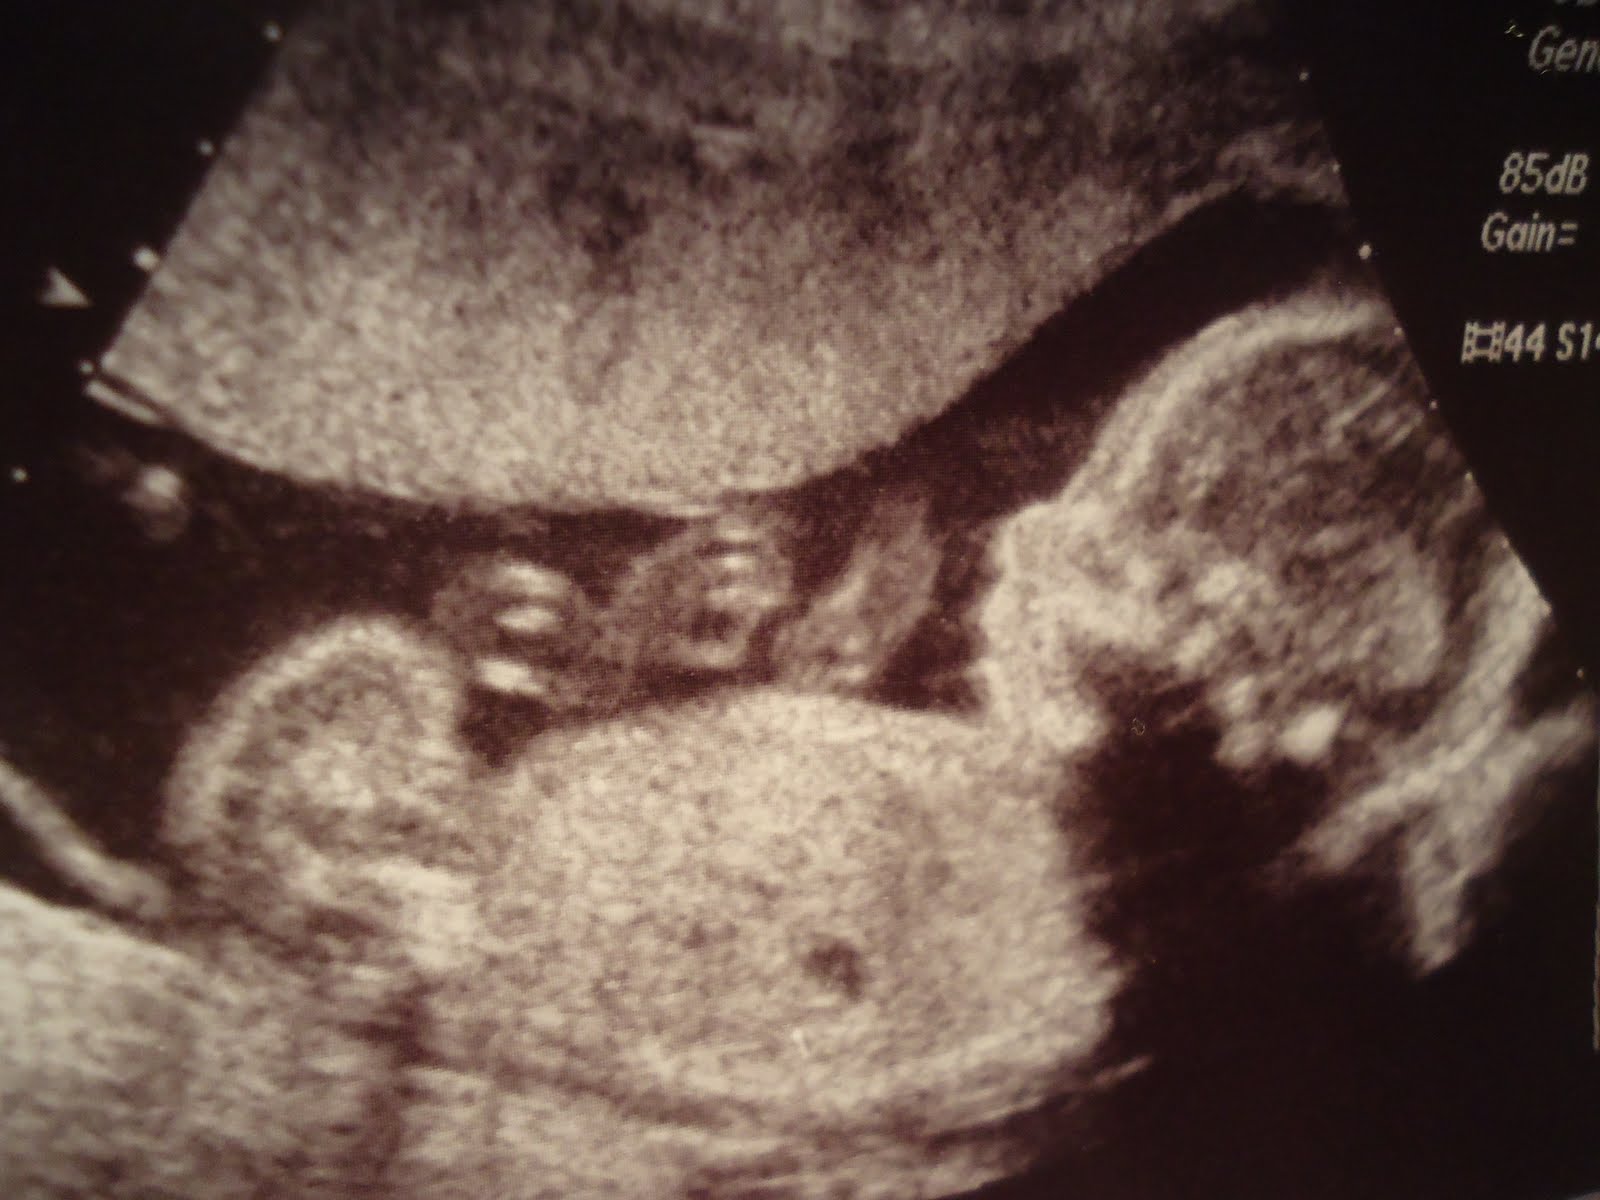

How To Prepare For Baby At 20 Weeks. You might be able to borrow baby clothes, furniture, and strollers from friends and family members with older children. Celebrate by doing something special for you—whether it’s a nice dinner, a new shirt or watching your favorite movie. Around 20 weeks, you�ll have an ultrasound, so the doctor can assess your baby�s growth and make sure all the organs are developing properly. Your baby’s skin thickens and develops layers under the vernix during the 20th week of pregnancy.

The average 20 week fetus weighs 10.2 ounces and measures 16.5 cm or 6.5 inches long. As your uterus expands, it pushes against your lungs, causing you to feel short of breath. The preparation is minimal for the scan, but here are a few do’s and don’t. We look at what a sonographer will check for at 20 weeks. It was a long wait to say the least. This discharge is called lochia, and it can contain blood, mucus, and uterine tissue from the female body.

But now it�s more common for women to be having their second ultrasound at 20 weeks gestation; Muscles are growing, and your baby. When you’re 20 weeks pregnant, your baby measures about 6”, about the length of an eggplant, and weighs about half a pound. Your baby is moving around and you may be able to feel it. Case scenarios and tried to prepare myself. Your baby’s skin thickens and develops layers under the vernix during the 20th week of pregnancy.

At 20 weeks pregnant, i had hope for my baby. At 20 weeks pregnant, the baby is as big as a banana/sweet potato. The first is generally offered at around 12. It�s becoming increasingly uncommon for pregnant women to have their very first ultrasound at 20 weeks, though this used to be the first opportunity for most pregnant mums to be able to see their baby inside the uterus. By 20 weeks most of your baby has developed such that screening of the organs is possible to assess for abnormalities.

Most women expect this to occur, but they don�t always expect it to continue for the next six weeks or so. Meanwhile, baby�s lungs are developing more this week. The scan can take a minimum of 45 minutes and sometimes up to an hour. This is likely when you can. Check mama’s uterus, fluid levels, and placenta;

We look at what a sonographer will check for at 20 weeks. Celebrate by doing something special for you—whether it’s a nice dinner, a new shirt or watching your favorite movie. 20 weeks down, 20 (ish) to go! Check mama’s uterus, fluid levels, and placenta; At 20 weeks pregnant, i had hope for my baby.